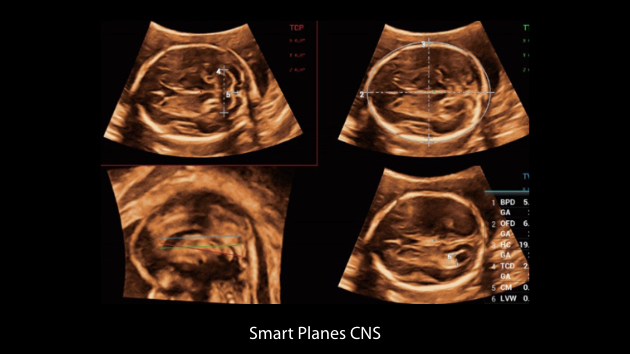

Nuewa I9 Elite Edition ├© progettato appositamente per l'assistenza sanitaria a donne e neonati e offre un'esperienza innovativa sviluppata sulla base di conoscenze approfondite relative a scenari clinici complessi, per risposte accurate e tempestive, nonch├® un'efficienza e un'esperienza utente eccezionali